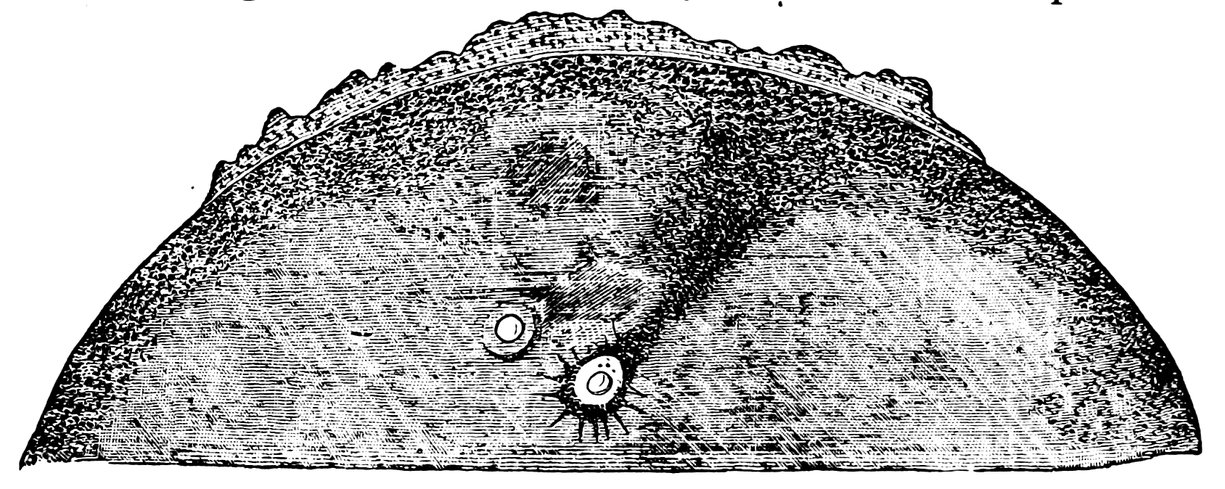

| 55. | First Stage. A. Entrance of a Spermatozoon into the Ovum of Ascaris Megalocephala. B. After preparations by M. Nussbaum. (Half of the ova only are depicted) | 306 |

| 56. | Ovum of Asterakanthion ten minutes after Fertilization | 306 |

| 57. | Fusion of Male Pro-nucleus and Female Pro-nucleus to form the Segmentation Nucleus of the Fertilized Ovum | 306 |

| 58. | Passage of Spermatozoon through the Zona Pellucida of the Ovum of Asterakanthion | 307 |

| 59. | Ovum of Scorpæna Scrofa Thirty-five Minutes after Fertilization | 307 |

| 60. | Male Pro-nucleus and Female Pro-nucleus in Fertilized Ovum of Frog, prior to the Formation of the Segmentation Nucleus | 307 |